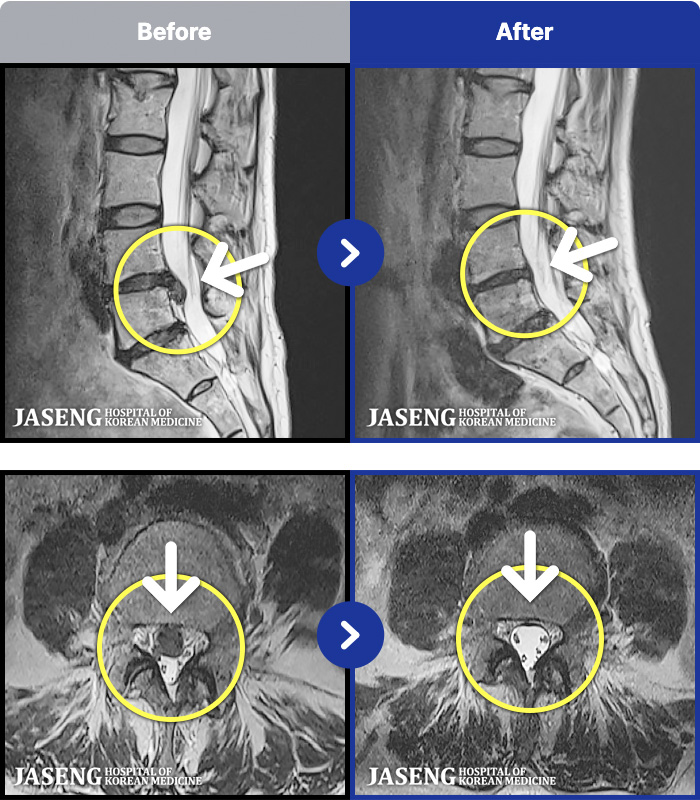

MRI ġ

1,301 MRI ũ ʸ Ȯϼ.